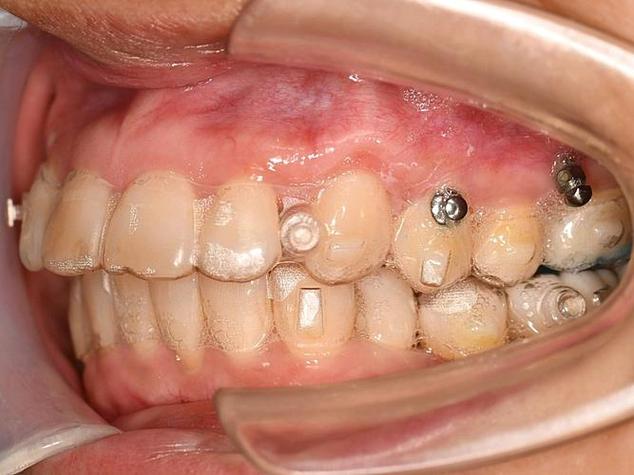

- 器械准备: 医生会使用专门的器械,通常是一个类似小扳手或螺丝刀形状的专用取钉器(有时也可能用持针器或蚊式钳,但专用工具更常见)。

- 医生会用器械稳稳地夹住或套住支抗钉的头部(暴露在牙龈表面的部分)。

- 医生会轻轻地、稳定地向逆时针方向旋转,支抗钉通常是自攻螺纹设计,取下时就是反向拧出。

- 轻柔取出: 一旦钉子开始松动,医生会感觉阻力减小,然后可以更轻松地将整个钉子从牙槽骨中旋出,整个过程通常只需要几秒钟到十几秒钟。